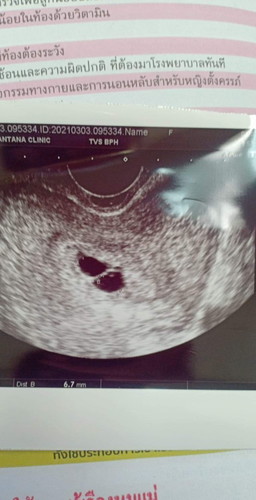

ครรภ์แฝดยินดีด้วยค่ะ แฝดคนละถุงซะด้วย

แฝดไหมคะ